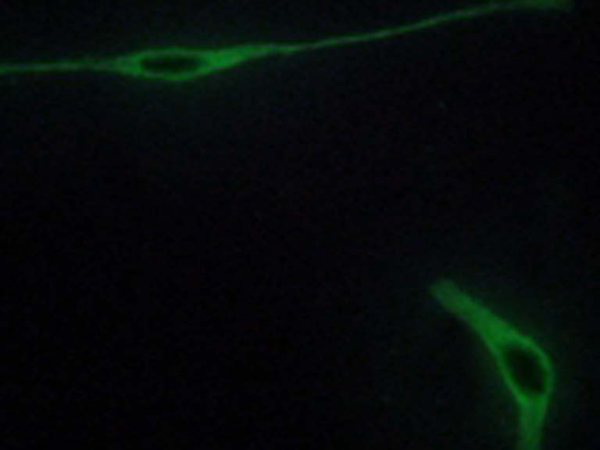

IF positive control: |

NIH/3T3 cells |

IF Recommend dilution: |

100-500 |